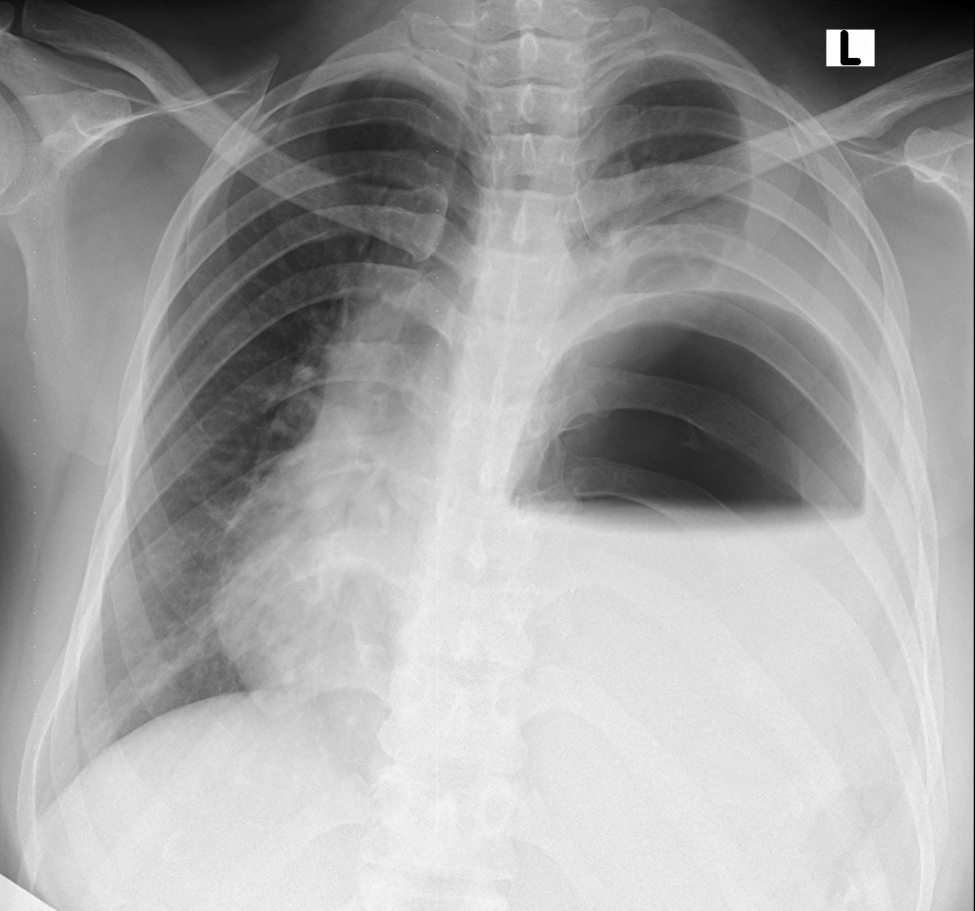

Figure 1. Chest x-ray at arrival showing an air-fluid level in the left hemithorax with contralateral mediastinal shift.

A 27-year-old woman presented to the emergency department with complaints of shortness of breath and cough with sputum for the last three days that had worsened since the morning of presentation. Her history was significant for gestational amenhorrea of 32 weeks. This was her second pregnancy. Her vital signs were within the normal limits. A physical exam revealed absent breath sounds on the left side and a gravid uterus of about 30 weeks. A chest x-ray was done which showed air fluid levels in the left chest with upward pointing meniscus. The authors’ differential included a diaphragmatic hernia, diaphragmatic eventration, hydatid cyst, and loculated empyema. An obstetrician was consulted, and after an examination, they declared that the patient was in labor. She delivered a healthy baby through normal vaginal delivery. After labor, she was comfortably lying in bed with normal vital signs and no active complaints. However, a little later, the patient started to become tachypneic and tachycardiac. Her respiratory rate was more than 50 per minute and heart rate was more than 140 per minute. An electrocardiogram was done which showed sinus tachycardia. She was shifted to the intensive care unit and was intubated for progressing respiratory failure. A nasogastric tube was passed and approximately more than two liters of gastric content was aspirated. An urgent echocardiogram was obtained which showed a right ventricle strain and a dilated Inferior vena cava without respiratory variation. The patient was urgently shifted for a computed tomography of the chest with intravenous contrast, which revealed a large diaphragmatic hernia on the left side. The stomach, omentum, splenic flexure of the colon, the descending colon, small bowel, spleen, and tail of the pancreas were all present in the left chest cavity. There was a mediastinal shift to the right, and the left lung was collapsed. The right lower lobe also showed signs of compression atelectasis.